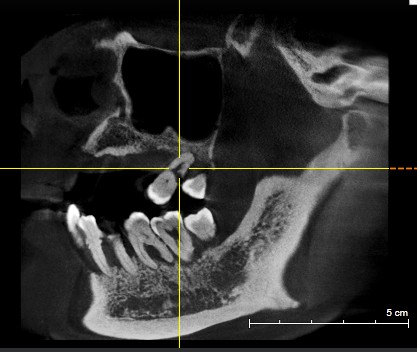

患者女,五十岁,近几年出现刷牙出血和牙齿的松动,甚至部分脱落,近期前来我院就诊。患者全身健康,否认糖尿病,否认家族病史。临床检查:口腔卫生差,可见大量菌斑,软垢。牙石+++,牙龈暗红。根面暴露,前牙部分脱落。X线示牙槽骨吸收至根尖1/3。

治疗计划:1拔除无法保留的牙齿。2牙槽骨吸收至根尖2/3以上的患牙进行根管治疗。3分次进行牙周刮治。4缺失牙修复。5定期维护